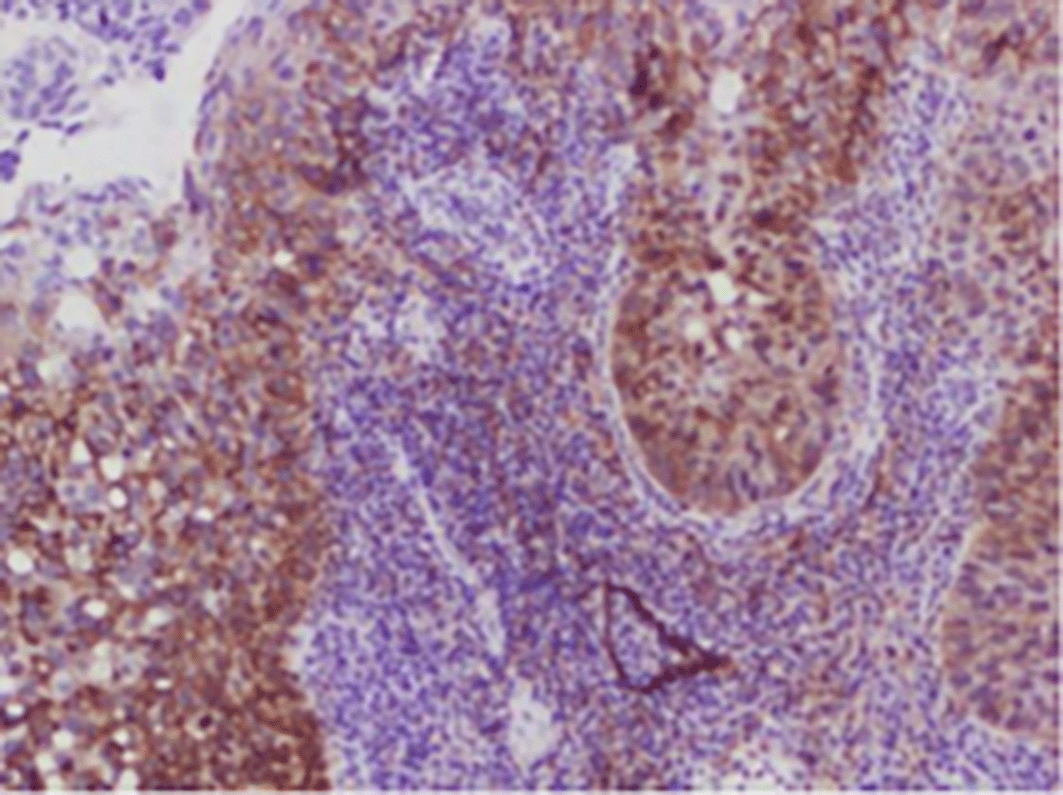

The IHC-stained slides were assessed separately by two pathologists. To avoid bias during assessment, they had no access to the patients’ clinical data. During the occurrence of inter-observer variation in assessment, specific slides were made to be viewed together, and their consensus opinion was taken into consideration ( Figures 1-4).

a18ea2fb-f248-4101-a9ac-0da1acc0b230_figure4.gif

Figure 4. Expression of PODOPLANIN.